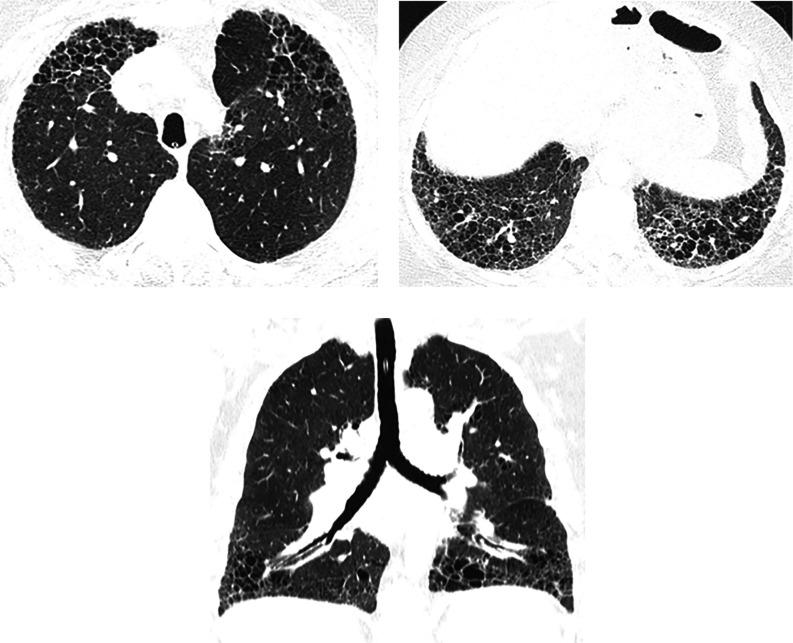

This American Thoracic Society, European Respiratory Society, Japanese Respiratory Society, and Asociación Latinoamericana de Tórax guideline updates prior idiopathic pulmonary fibrosis (IPF) guidelines and addresses the progression of pulmonary fibrosis in patients with interstitial lung diseases (ILDs) other than IPF. A committee was composed of multidisciplinary experts in ILD, methodologists, and patient representatives. ) Update of IPF: Radiological and histopathological criteria for IPF were updated by consensus. Questions about transbronchial lung cryobiopsy, genomic classifier testing, antacid medication, and antireflux surgery were informed by systematic reviews and answered with evidence-based recommendations using the Grading of Recommendations, Assessment, Development and Evaluation (GRADE) approach. ) Progressive pulmonary fibrosis (PPF): PPF was defined, and then radiological and physiological criteria for PPF were determined by consensus. Questions about pirfenidone and nintedanib were informed by systematic reviews and answered with evidence-based recommendations using the GRADE approach. ) Update of IPF: A conditional recommendation was made to regard transbronchial lung cryobiopsy as an acceptable alternative to surgical lung biopsy in centers with appropriate expertise. No recommendation was made for or against genomic classifier testing. Conditional recommendations were made against antacid medication and antireflux surgery for the treatment of IPF. ) PPF: PPF was defined as at least two of three criteria (worsening symptoms, radiological progression, and physiological progression) occurring within the past year with no alternative explanation in a patient with an ILD other than IPF. A conditional recommendation was made for nintedanib, and additional research into pirfenidone was recommended. The conditional recommendations in this guideline are intended to provide the basis for rational, informed decisions by clinicians.

美国胸科学会、欧洲呼吸学会、日本呼吸学会和拉丁美洲胸科学会更新了特发性肺纤维化(IPF)指南,涵盖了除 IPF 以外的间质性肺疾病(ILD)患者肺纤维化的进展。一个委员会由ILD 的多学科专家、方法学家和患者代表组成。

• 更新 IPF:通过共识更新了 IPF 的放射学和组织病理学标准。关于经支气管肺冷冻活检、基因组分类器检测、抗酸药物和抗反流手术的问题,通过系统评价提供信息,并使用基于证据的推荐和 Grading of Recommendations, Assessment, Development and Evaluation (GRADE) 方法回答。

• 进行性肺纤维化(PPF):定义了 PPF,然后通过共识确定了 PPF 的放射学和生理学标准。关于吡非尼酮和尼达尼布的问题,通过系统评价提供信息,并使用基于证据的推荐和 GRADE 方法回答。

• 更新 IPF:有条件建议将经支气管肺冷冻活检视为具有适当专业知识的中心替代外科肺活检的可接受方法。未对基因组分类器检测提出建议或反对。有条件反对使用抗酸药物和抗反流手术治疗 IPF。

• PPF:PPF 定义为在过去一年中,在非 IPF 的ILD 患者中,出现至少三个标准中的两个(症状恶化、放射学进展和生理学进展),且无其他解释。建议使用尼达尼布,并建议对吡非尼酮进行进一步研究。